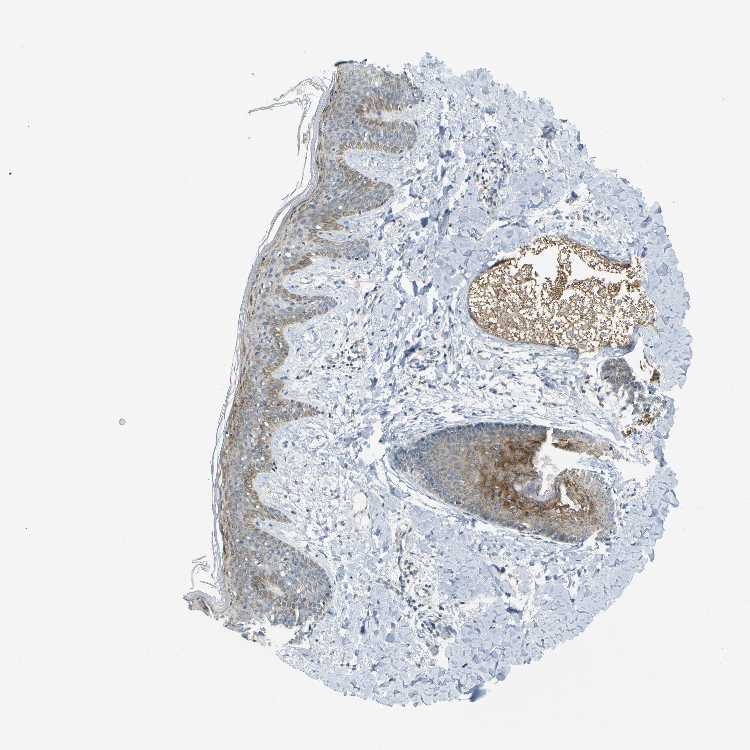

TISSUE PRIMARY DATA SKIN Show tissue menu

SKIN 1 - Antibody stainingi

Antibody staining in the annotated cell types in the current human tissue is reported as not detected, low, medium, or high, based on conventional immunohistochemistry profiling in selected tissues. This score is based on the combination of the staining intensity and fraction of stained cells.

Each image is clickable and will lead to virtual microscopy that enables deeper exploration of all samples and also displays staining intensity scores, fraction scores and subcellular localization as well as patient and tissue information for each sample.

Antibody HPA011861Antibody HPA012145

Langerhans MediumLow

Fibroblasts Not detectedLow

Keratinocytes MediumMedium

Melanocytes MediumMedium

SKIN 2 - Antibody stainingi

Epidermal cells LowMedium